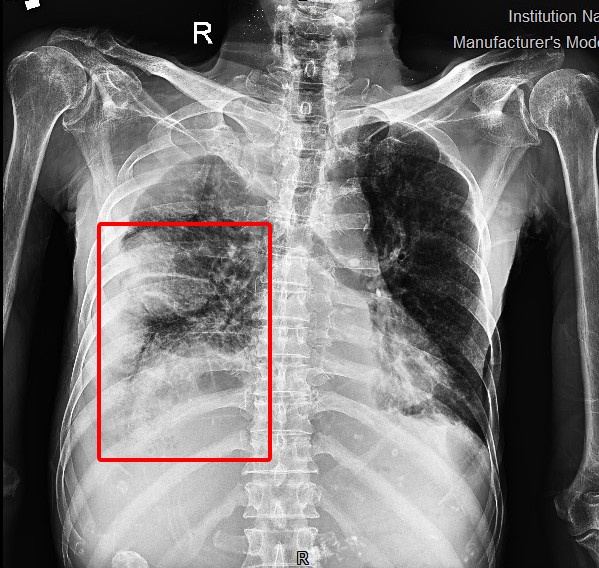

Ông S. bị tràn dịch màng phổi sau tai nạn. Ảnh: BVCC.

Sau xét nghiệm và thăm khám cận lâm sàng, các bác sĩ phát hiện bệnh nhân tràn mủ phổi phải cùng nhiều ổ áp xe, đông đặc thùy dưới phổi trái. Ông được chẩn đoán hôn mê CRNN - suy hô hấp cấp. Sau khi cấp cứu, các bác sĩ tiếp tục chuyển bệnh nhân lên điều trị tại khoa Hồi sức Tích cực - Chống độc.

Kết quả chụp CT-Scanner cho thấy bệnh nhân bị tràn dịch khoang màng phổi hai bên, tiên lượng tử vong cao nếu không khẩn trương xử trí sạch ổ cặn, kích phổi phải giãn nở để thông khí.